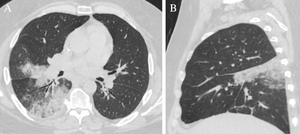

Chest radiography revealed a new right perihilar opacity (Figure 2). Axial images of a CT scan of the chest showed ground glass and consolidative opacities within the posterior superior aspect of the right middle lobe and superior segment of the right lower lobe (Figure 3a). Sagittal images showed wedge shaped airspace disease (Figure 3b). Given the patient was initially felt to have community-acquired pneumonia, he received 7 days of ceftriaxone and doxycycline, but he continued to have frequent cough and worsening “back” pain exacerbated by cough. Upon re-review of the patient’s initial chest CT (Figure 3), recognition of pulmonary infarction as a potential explanation for the patient’s symptoms led to acquisition of a contrast-enhanced chest CT, which revealed interval increase of the patient’s previously recognized PE within the right interlobar pulmonary artery, with new occlusion of the right lower lobe pulmonary artery and vessel expansion compatible with acute on chronic thrombosis (Figure 4a). The study additionally demonstrated progression of alveolar edema and hemorrhage within the right middle and right lower lobes (Figure 4b). Thrombectomy was considered; however, as there was no evidence of right heart strain or hemodynamic instability, this was deferred. Rivaroxaban was stopped, and a heparin drip was initiated with a 5-day bridge to warfarin. Warfarin was chosen over an alternative direct-acting oral anticoagulant (DOAC) due to concern for DOAC malabsorption related to the patient’s sleeve gastrectomy, as well as a desire for international normalized ratio (INR) monitoring.